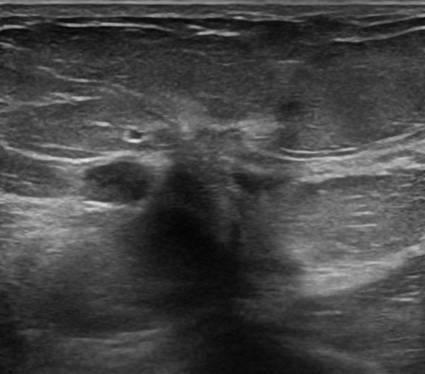

Ung thư vú

» Thông tin: Nữ giới – 50 tuổi.

» Lâm sàng: Khối tuyến vú.